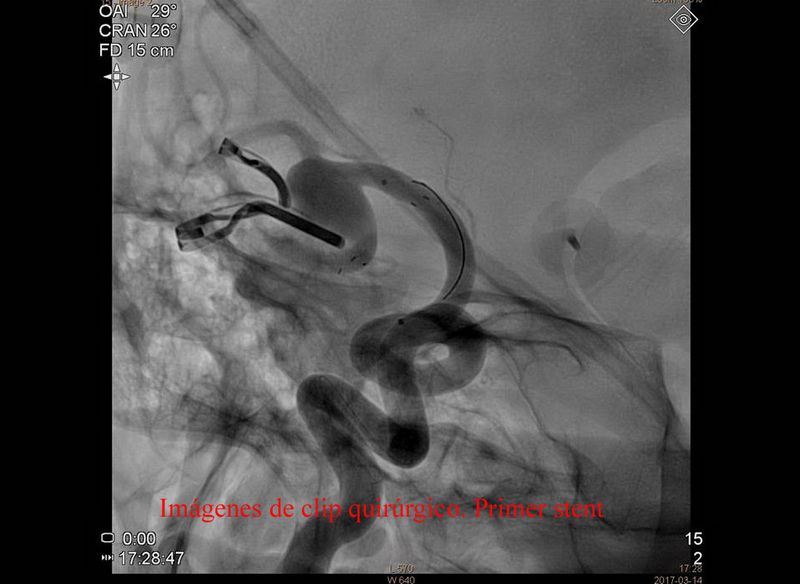

Aneurisma trat quirurgicamente